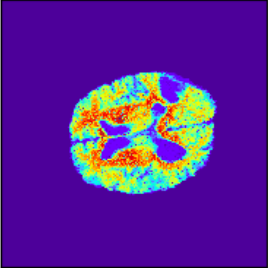

To illustrate the performance of the proposed technique for clinical applications, MR images were chosen. The performance of the technique was tested by registering multi-modal MR image pairs. In a clinical setup, it is common practice to register images or volumes acquired from different imaging modalities or MR sequences. Figure 3 illustrates the degree of overlap between moving images (a) T2 and (f) T1 weighted sequence on fixed images (b) T2 and (g) T2 weighted sequence respectively. It was observed using the registration proposed in this manuscript, the dice score improved from 0.44 (prior to registration) to 0.91 (post registration) for multimodal sequences. On the BraTs data, figure 4 (a-d) illustrates the performance of our method based on other metrics such as Dice, SSMI, MI, and MSE respectively. As the key points were generated by utilizing only the feature maps of the initial two layer of the network, the spatial dimension of the data has little impact on the performance. Unlike other CNN based technique which considers the entire image for estimating the transformation parameters, our method requires CoMs which reduces the dimensionality from (m n n) to (m 2), where m denotes the number of feature maps and n is the pixel dimension of the feature map. This aids in lowering execution time drastically. The proposed pipeline also consists of an uncertainty estimator. uncertainty maps illustrated in all the above examples show the region of higher variance in registration, which in turn suggests surgeons/ observers to make better decisions. Pixel region with red color indicates the larger variance region while blue indicated low variance region. For example in figure 3 (e) shows that the central region of the brain has higher pixel-wise variance as compared to the outer part of the brain. The performance of the algorithm on volumes on the same modality is illustrated in figure 3 (a-e)